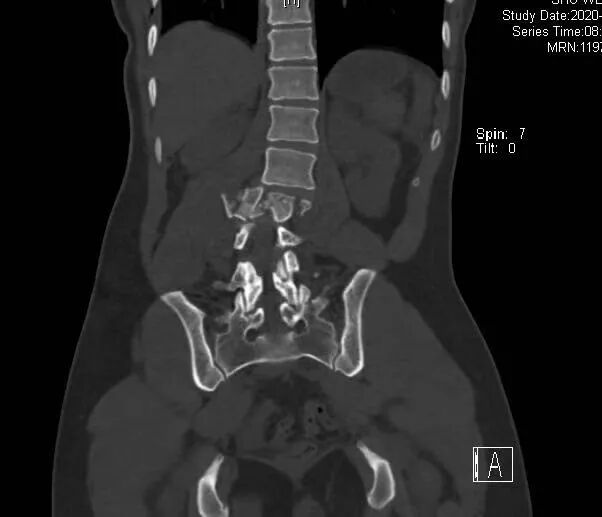

在一个十字路口,突然一辆小轿车从她的斜后方冲了上来,她连人带车被卷入车底。被卷进车底的那一刻,车子仍继续在向前开,小舒听到女司机一声尖叫,下意识以为自己就要死了。车停了下来,她发现头还能动,意识也清晰,开始呼救。很快,路人们把她从车底救了出来。等老公和120救护车赶来,小舒可能是放心了,之后的事她说全都不记得了。丈夫小杨说,在被送进手术室的那一刻,迷迷糊糊的小舒一直在说:“我想见我女儿。”虽然表面上看不到任何出血,但事实上小舒伤得很重,尤其是身体右侧。她被诊断为多发性创伤,肝破裂、腹腔出血、腰椎爆裂性骨折,肋骨多发性骨折,脊髓损伤,腰2-4神经根断裂……从CT上看,小舒的腰椎严重移位,被挤成了“S”形,动脉周围还有呈三角形的碎片,随时可能有生命危险。![]()

术前CT片,小舒的腰椎像完全断开了一样,严重错位。